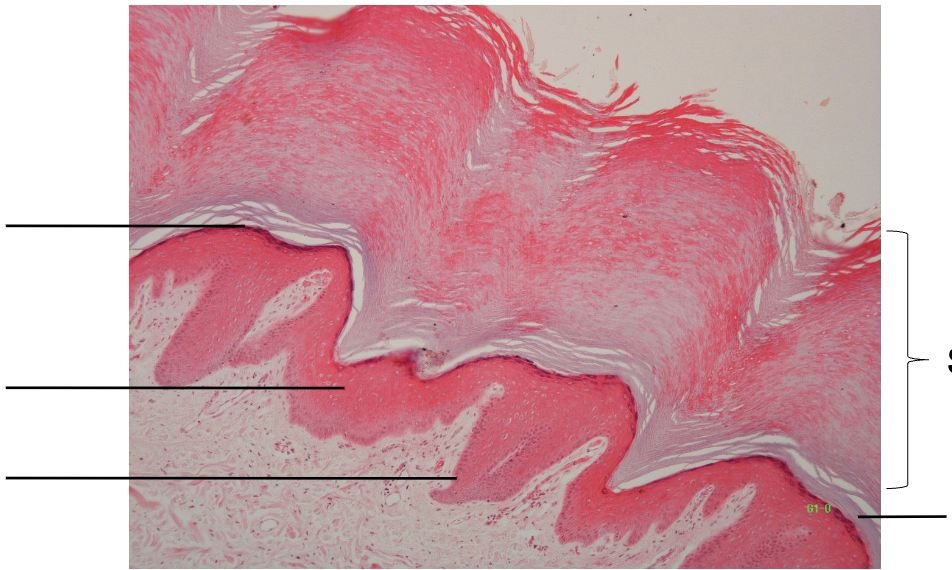

Label strata of epidermis

Thick skin: Strata of epidermis